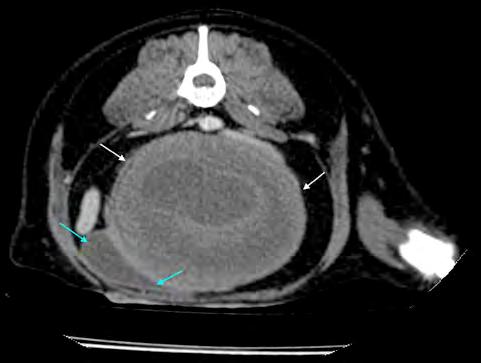

Por otra parte, un 58,8 % (70/119) mostraron características de multirresistencia, considerándose como tal las cepas de SP resistentes a más de tres antibióticos pertenecientes a tres grupos diferentes, con una resistencia media a 5 grupos de antibióticos diferentes (rango 3-7) (Fig. 1). Los aislados que podrían considerarse como “extensive drug resistant” (o, por sus siglas en inglés, XDR, resistentes a 7 grupos de antibióticos diferentes) fueron el 14 % de los aislados MDR (10/70), no observándose ninguna cepa de SP “pandrug resistant” (o PDR, resistente a todos los grupos de antibióticos testados).

Figura 1. Porcentaje de cepas de Staphylococcus pseudintermedius multirresistentes en función del número de grupos de antibióticos a los que muestran resistencia.

El grupo antibiótico al que las cepas aisladas mostraron un mayor porcentaje de resistencia fue el de los macrólidos con un 87 % de muestras resistentes a la eritromicina, seguido de las lincosamidas con un 58 % de resistentes a clindamicina. En el extremo opuesto se situaron los aminoglucósidos con un 21 % de cepas resistentes a la gentamicina y un 1,8 % a la amikacina. La rifampicina mostró un 9 % de aislados resistentes en las 45 muestras en las que se obtuvo este dato (Fig. 2). La resistencia a tetraciclinas y fluoroquinolónicos se situó en un 49 % y 45 %, respectivamente. La resistencia

a los distintos grupos de antibióticos testados.

Figura 2. Porcentaje de resistencia de los aislados de Staphylococcus pseudintermedius (n=119) frente